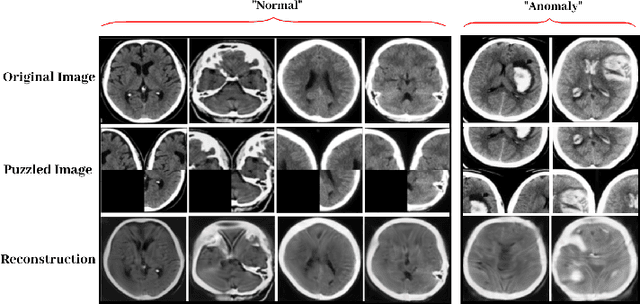

Abstract:Autoencoder (AE) has proved to be an effective framework for novelty detection. However, they do not typically show promising results on other kinds of real-world datasets, which are exhibiting high intra-class variations, such as CIFAR-10. AEs are not generally able to learn a latent space that solely captures common features of the normal class, resulting in both high false positive and false negative rates due to modeling features that are irrelevant to the normal class. Recently, self-supervised learning has shown great promise in representation learning. To this end, we propose a new AE framework that is trained based on solving puzzles on randomly permuted image patches. Based on this framework, we achieve competitive or superior results compared to SOTA anomaly detection methods on various toy and real-world datasets. Unlike many competitors in this field, the proposed framework is stable, has real-time performance, more general and agnostic to choices of the model hyper-parameters, can work effectively under small sample size settings, and does not require unprincipled early stopping.